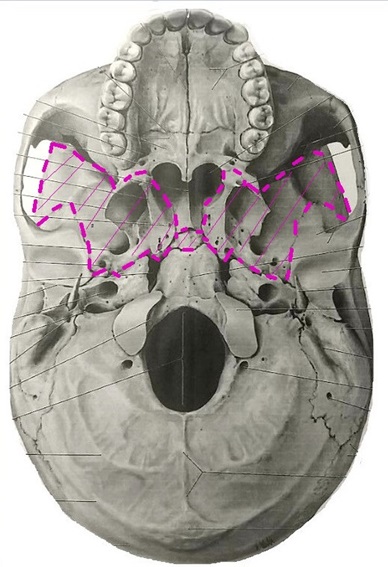

また頭蓋骨矯正

を行うと個人差は

ありますが左の図のように頭蓋骨が動い

て黄色の車線が動きオレンジ色の〇の位

置が変化する事により上顎の位置が変わ

り嚙み合わせが改善する場合があります

顎を上から見る解剖図

上顎を下から見立ててます

顎関節

上顎を真下から見立てます

青い〇印は外後頭隆起

(がいこうとうりゅうき)です